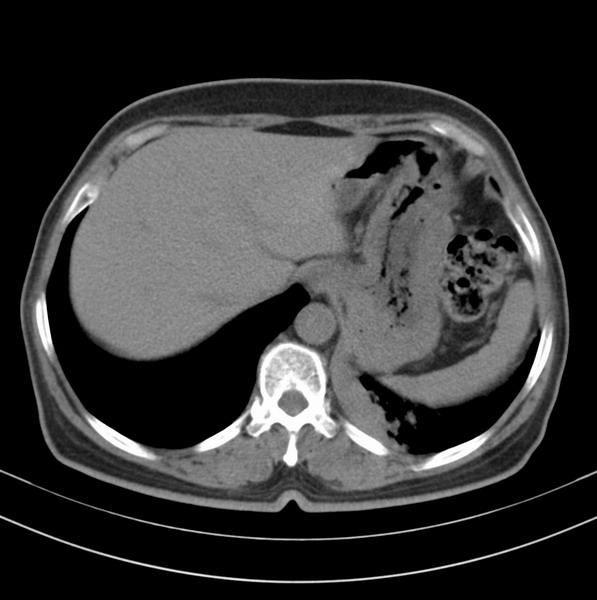

女、63

咳嗽、胸痛四个月

包绕左下肺基底段的不规则的软组织肿块,段支气管腔变形、狭窄及阻塞性炎症,病变区不规则强化,又是老年女性支持楼上看法。

典型病例:左下肺基底段中央型肺癌,相应支气管狭窄并阻塞性炎症